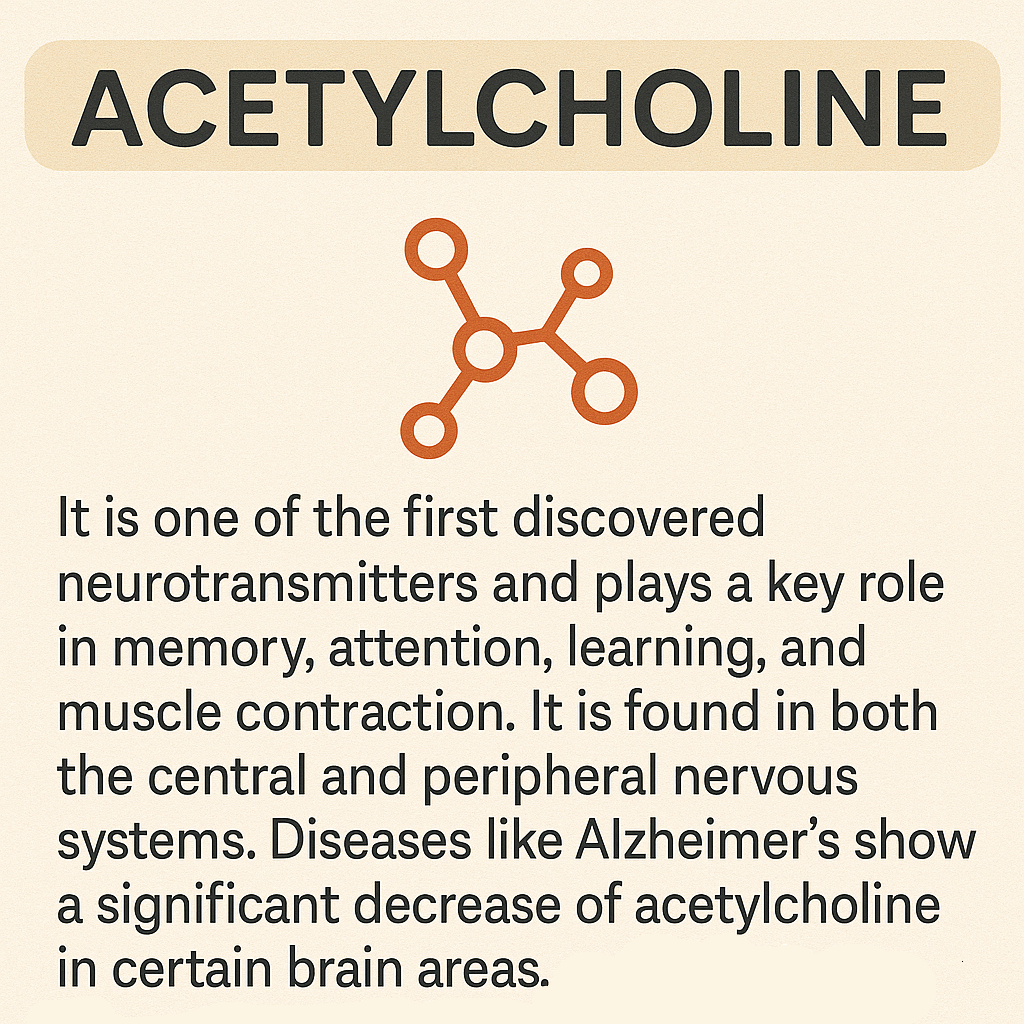

Neurotransmisores

Son sustancias químicas que permiten la comunicación entre las neuronas en el sistema nervioso y piezas fundamentales del engranaje cerebral. Sin ellos, no podríamos movernos, sentir, pensar ni aprender. Actúan como mensajeros que transmiten señales de una célula nerviosa a otra a través de la sinapsis y reforzada por la mielina. Esta función es fundamental para el funcionamiento del cerebro y, en general, del organismo, ya que regula desde procesos automáticos como la respiración o el ritmo cardíaco, hasta funciones complejas como el aprendizaje, la memoria, las emociones y la conducta.

Cuando una neurona se activa, libera neurotransmisores en la sinapsis. Estas moléculas se acoplan a receptores específicos en la neurona siguiente, generando un nuevo impulso eléctrico o modificando la actividad de esa célula. Posteriormente, los neurotransmisores pueden ser degradados, reciclados o reabsorbidos por la neurona original mediante un proceso llamado recaptación.

El equilibrio químico de los neurotransmisores es delicado. Su exceso o déficit puede causar trastornos como ansiedad, depresión, esquizofrenia, Alzheimer o Parkinson.